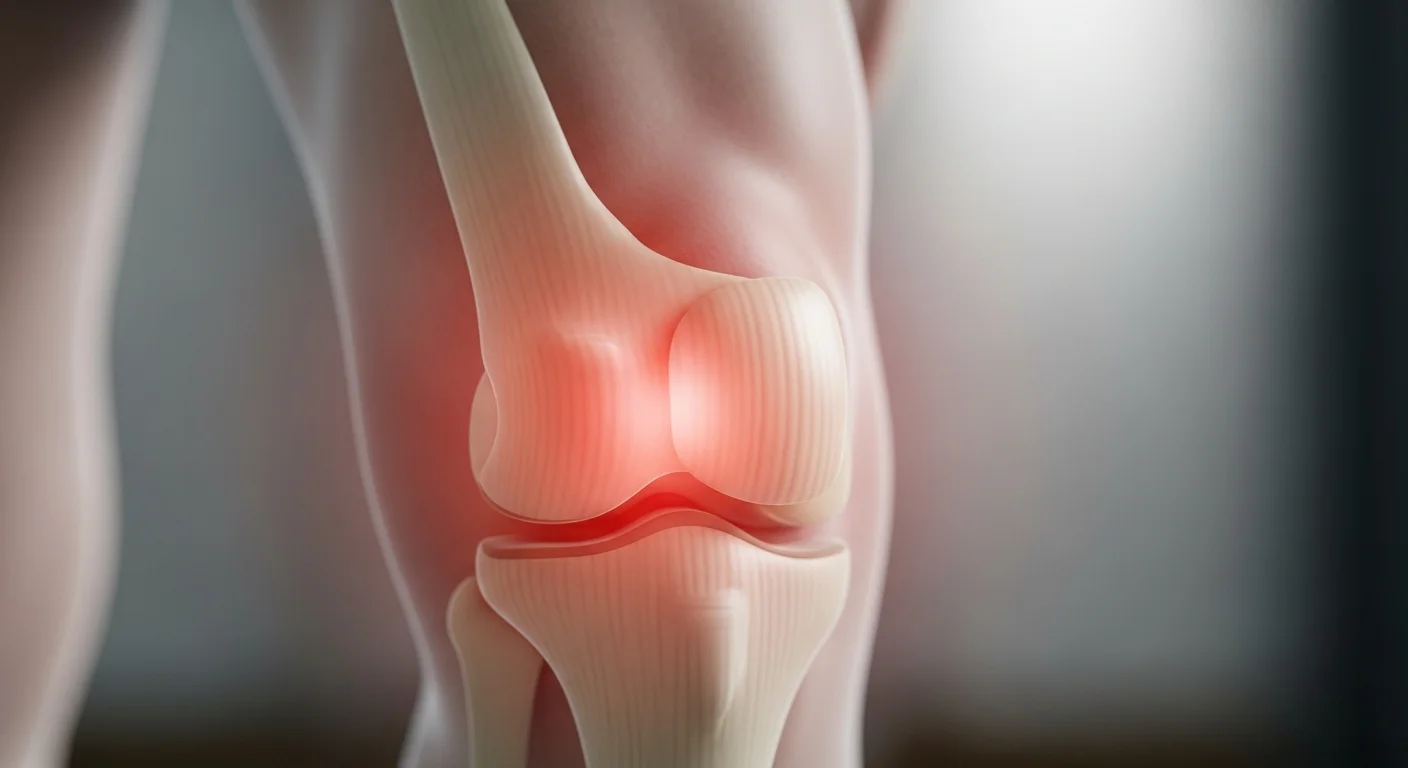

Ide o chronické preťaženie a degeneratívne zmeny v patelárnej šľache, ktorá spája jabĺčko s píšťalou. Táto šľacha je kľúčová pri narovnávaní kolena, skákaní, behu a dopade, pretože prenáša silu zo stehenného svalu. Opakovaný stres vedie k vzniku mikrotrhlín a štrukturálnym zmenám v šľache. Ak sa týmto mikrotraumám neposkytne čas na zahojenie, problém sa stáva chronickým.

Hlavným a dominantným príznakom je bolesť priamo pod jabĺčkom, bolesť sa typicky zhoršuje pri záťaži,na dotyk môže byť oblasť patelárnej šľachy citlivá, opuchnutá, bolestivá.